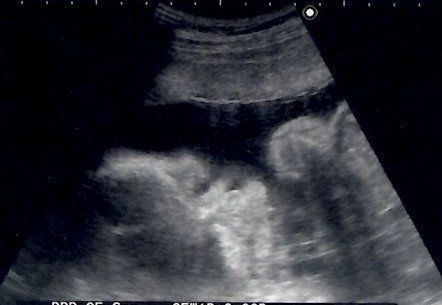

妊娠30週目のエコー写真 マタニティー旅、決行

この頃の私は、軽い眠気がある以外は体調も安定し、マタニティーヨガをやったり、妊婦同士のお茶会を開催して赤ちゃん用品の情報を交換したりと、充実したマタニティーライフを送っていました。そして満を持して出産前最後の思い出作りにマタニティー旅を決行。通常ではなかなか行けないオーシャンビュー&露天風呂付きの豪華な部屋に宿泊し、夫婦ふたりだけの最後の旅行を楽しみました。